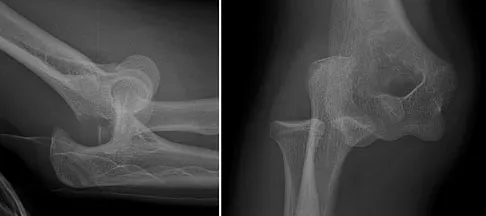

Question 12

Figure 12 shows a lateral radiograph of the elbow. What is the most likely diagnosis?

Explanation